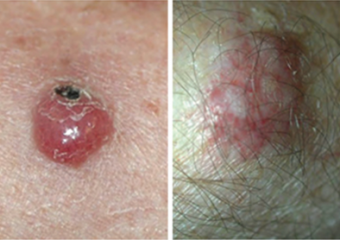

Basal cell carcinoma presenting as an open sore on the ear. Photo: International Skin Imaging Collaboration at isic-archive.com

Basal cell carcinoma presenting as a pink growth. Photo: International Skin Imaging Collaboration at isic-archive.com

A small pink growth with a slightly raised, rolled edge and a crusted indentation in the center. (BCC)